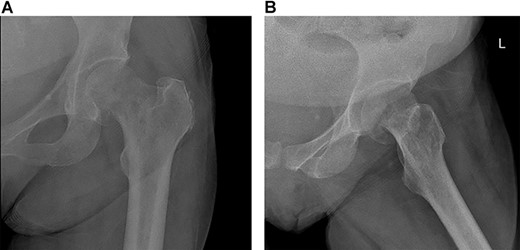

MRI showing displaced fracture noted at the left femoral neck and subcapital right femoral neck fracture with minimal reactive changes.

A 60-year-old lady, community walker with no assistance of a cane or walker, known to have PMF on ruxolitinib. She was diagnosed with PMF in a different hospital 4 months prior to presentation (Fig. 1). She presented to our clinic with 8-month history of progressive left hip pain and was not able to bear weight since the initial episode of pain without the use of analgesia. The pain was relieved with analgesics and intra-articular injections previously, which stopped showing benefits prior to presenting to our clinic. The patient did not report any history of trauma or falling down, no fever or loss of appetite. Range of motion of the hip was severely restricted due to pain. Greater trochanter tenderness was noted on examination. Initial x-rays were ordered (Fig. 2) and revealed a possible left neck of femur fracture, which prompted us to order an MRI that showed a displaced neck of femur fracture in the left hip and a non-displaced neck of femur fracture of the right hip (Fig. 3). Surgical intervention for the left neck of femur fracture was offered to the patient, while the right neck of femur fracture was asymptomatic and conservative treatment was preferred. The patient favored surgery and requested to be done as soon as possible. She was admitted from the clinic to the ward for preoperative clearance and planning.